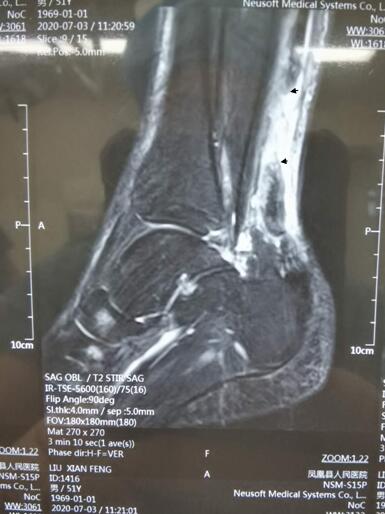

术前核磁共振提示跟腱断裂(箭头处)

入院后,经过核磁共振检查,诊断为“左跟腱断裂”。根据患者的情况和手术诉求,骨二科主任朱光宏为刘先生制定了手术方案——采用跟腱断裂通道吻合技术进行跟腱微创手术,并亲自主刀。